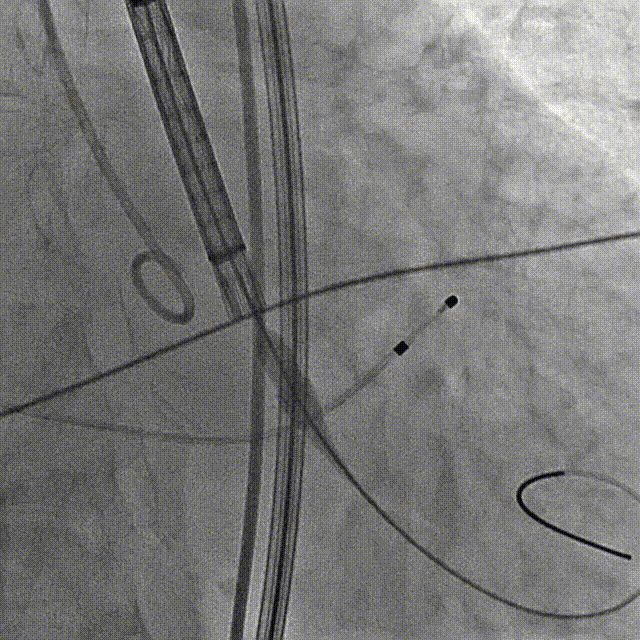

定位造影

初始定位及释放